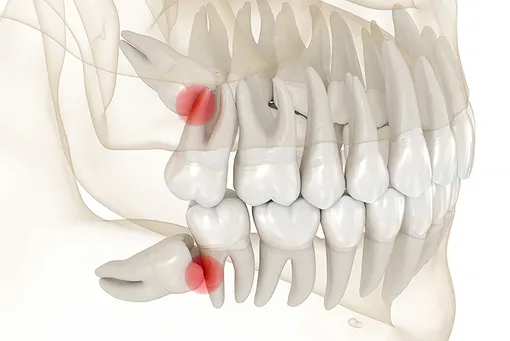

- зуб растет горизонтально и давит на соседние. Он вызывает или скоро будет вызывать дискомфорт, судя по снимкам.

При неправильном прорезывании третьих моляров под угрозой оказывается весь зубной ряд, поэтому их следует убрать. Однако благодаря методам функциональной ортодонтии можно избежать удаления. Не исключено, что после расширения челюстей зубы изменят положение и прорежутся вертикально. Своевременная диагностика дает возможность прогнозировать особенности роста восьмерок и не избавляться от них «на всякий случай».

Необходимо провести диагностику: клинико‑рентгенологический осмотр, панорамный снимок, при сложной анатомии – компьютерную томографию. При усилении боли, нарастании отека лица и шеи, лихорадке, затрудненном дыхании или глотании ситуация становится экстренной – нужно попасть к специалисту как можно быстрее.

При скученности зубов специалисты часто рекомендуют убрать третьи моляры. Если они прорезываются под наклоном, то могут принести немало неприятностей. Поэтому лучше вовремя провести точную диагностику и избавиться от них.